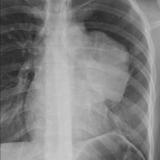

Case 9 Thymoma PA